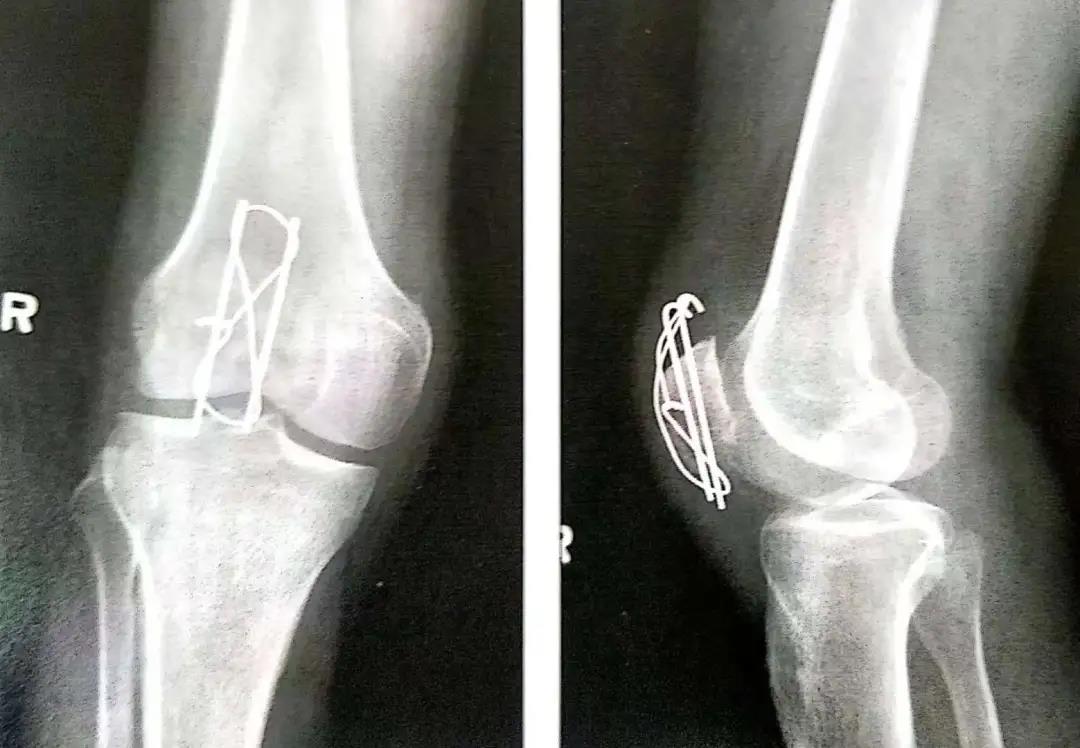

- 两平行克氏针的末端剪断后在张力环上翻转180°,上下两端埋入骨内以防止其移位。

- 髌骨重建一旦完成,内外侧支持带从各自的上端用 #1可吸收缝线开始修复以恢复其对髌骨的作用。

- 在关闭伤口前用术中透视或X线评估骨折复位和内置物的位置情况。